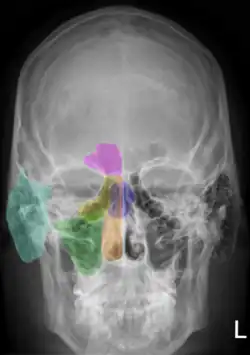

Рентгеноанатомия органов грудной клетки.

Рентгеноанатомия органов грудной клетки. Зелёным обозначены трахея и крупные бронхи, синим — ветви лёгочных артерий, красным — дуги тени сердца, цифрами отмечены сегменты лёгких.

При изучении рентгеноанатомии органов грудной клетки обращают внимание на рентгеновскую структуру видимых костей и мягких тканей грудной клетки; форму и прозрачность для рентгеновских лучей областей, на которые проецируется лёгочная ткань (так называемых «лёгочных полей»), а также их структуру, сформированную тенями сосудов лёгких («лёгочный рисунок»); расположение и структурность корней лёгких; положение, форму куполов диафрагмы и синусов плевральных полостей; форму и размеры тени средостения (в том числе сердца).